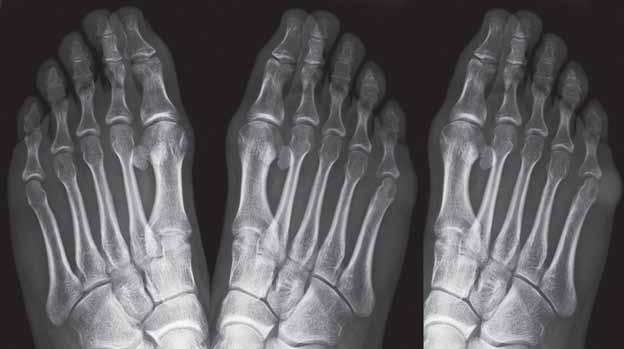

Poszerzenie i wzmożone wysycenie cienia tkanek miękkich okolicy stawu MTP 5 L od strony bocznej (oznaczone kolorem szarym), w bocznej części głowy 5 kości śródstopia lewego obecna pojedyncza geoda (oznaczona kolorem żółtym).